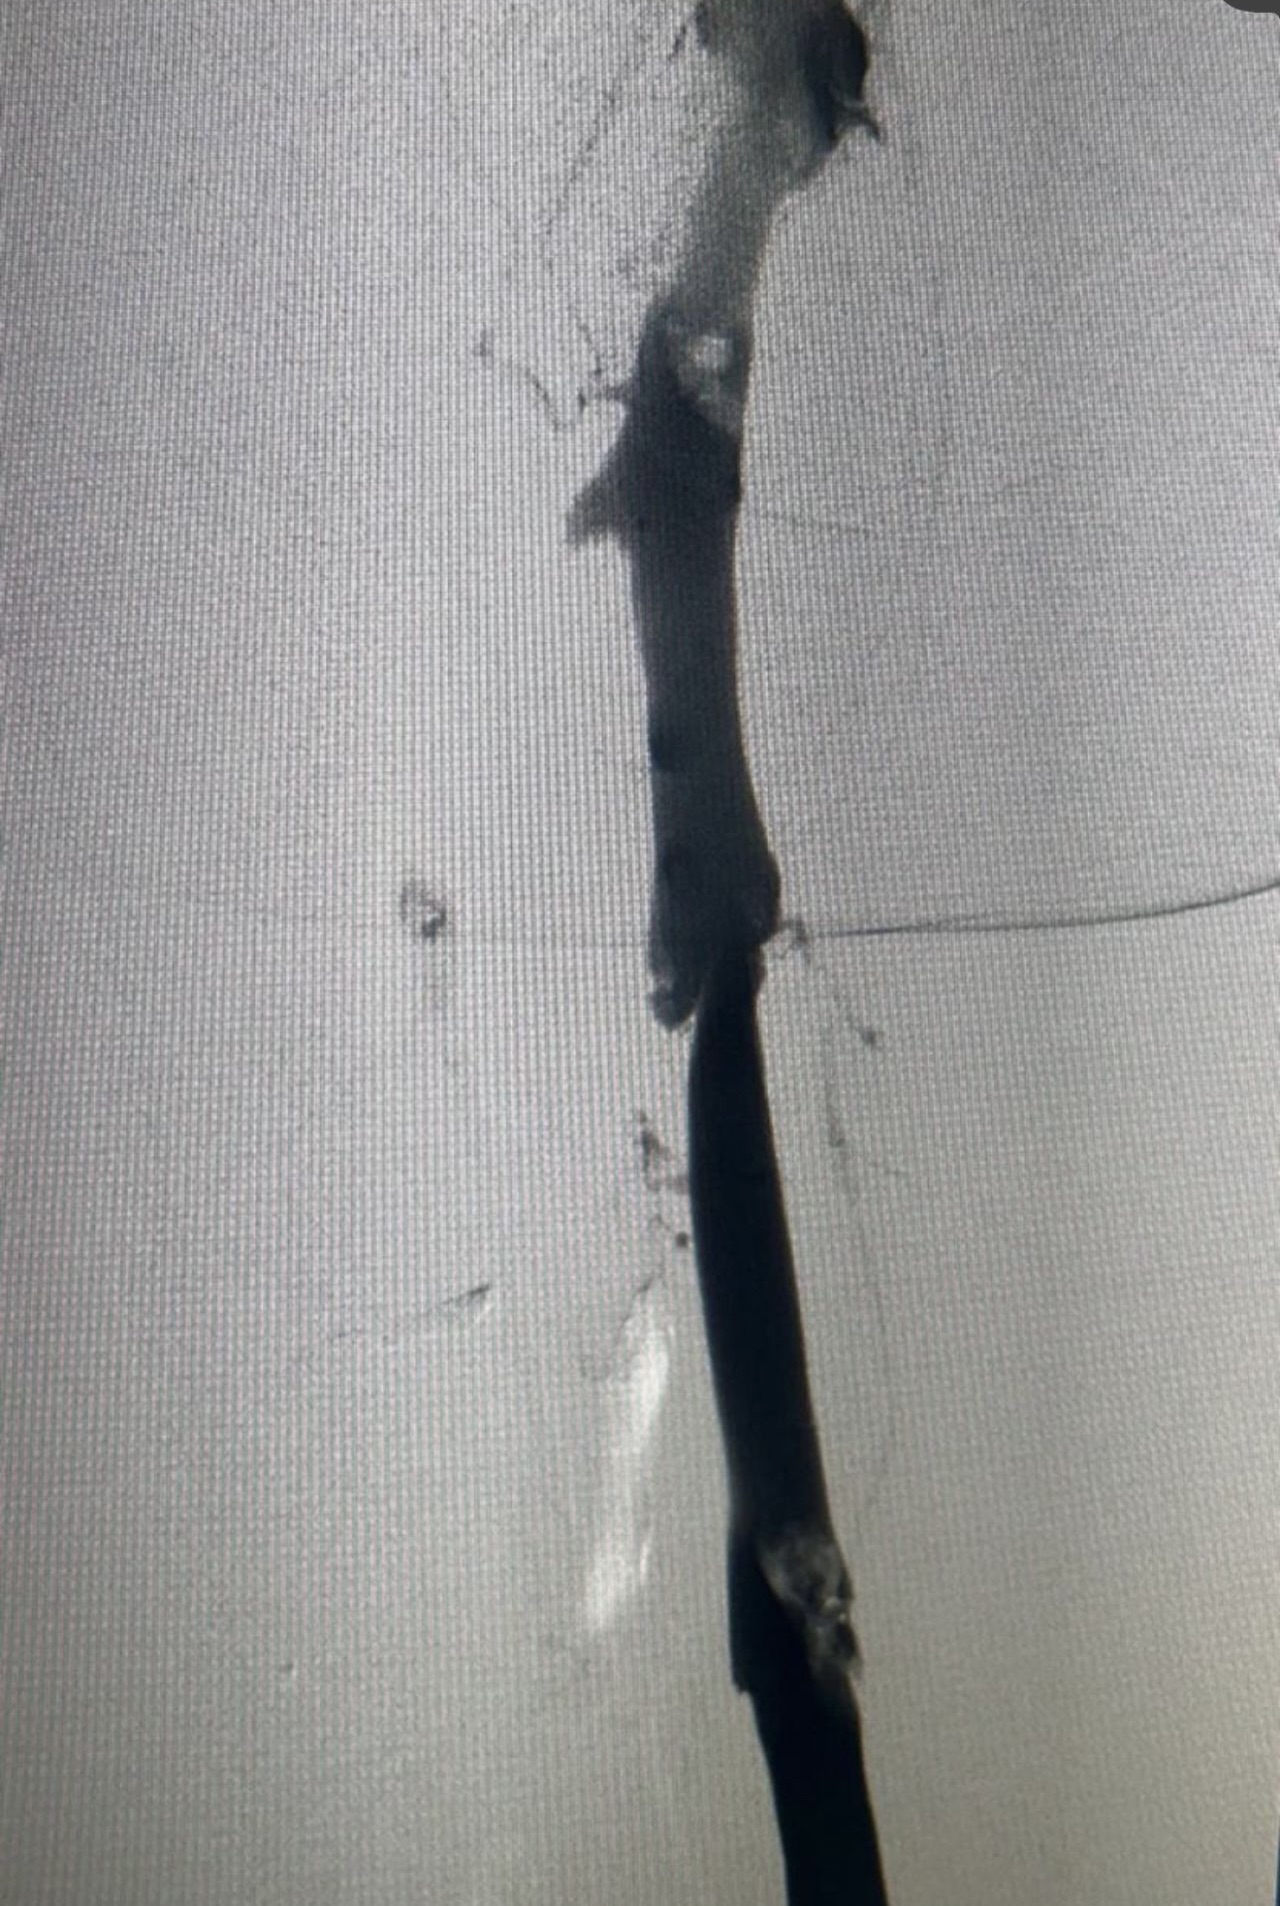

”Rapid Revascularization for Iliofemoral DVT

Acute extensive iliofemoral DVT demands a definitive solution.

The Case: Complete occlusion of the right iliac and femoral veins.

The Procedure:

1. Transpopliteal Access for direct control.

2. Mechanical Thrombectomy using the Penumbra 16 catheter for rapid clot aspiration.

3. Adjunctive Balloon Angioplasty to address underlying venous stenoses and ensure a durable result.

The Outcome: Immediate restoration of flow, resolution of symptoms, and a significant reduction in the risk of Post-Thrombotic Syndrome.

A powerful, minimally invasive approach that changes the patient’s trajectory.”